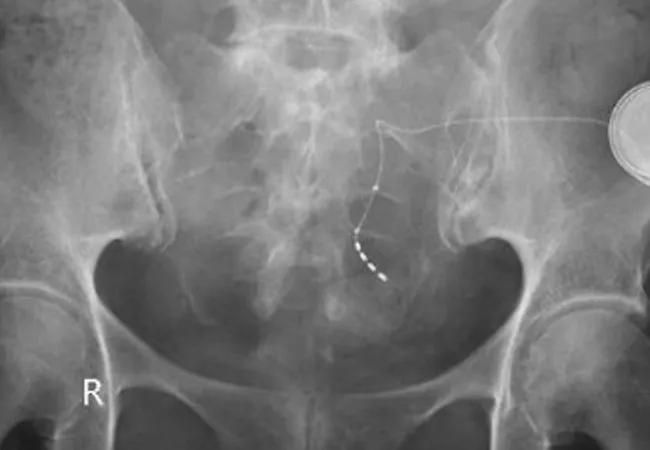

Is Sacral Neuromodulation a Viable Therapy After Proctectomy?

Outside of the United States, posterior tibial nerve stimulation (Horrocks et al, Wexner) may be utilized but has limited efficacy. The benefits of sacral neuromodulation have been confirmed in patients with sphincter defects, following sphincter repair and with pudendal neuropathy. Less well-established is the potential benefit of sacral neuromodulation in patients who have had rectal resections with neorectal reconstructions (Mizrahi et al).

In order to help fill our void in knowledge about the potential benefits of sacral neuromodulation in this setting, Mege and coworkers from France identified 16 patients who underwent sacral neuromodulation for neorectal reconstruction following coloanal anastomosis, colorectal anastomosis, or ileal pouch and anastomosis.

The authors found significant decreases in the number of stools per day, the number of fecal incontinent episodes, urgency, the low anterior resection (LAR) score and the Wexner (Cleveland Clinic) Incontinence Score1 following sacral neuromodulation in the six patients in whom a restorative proctocolectomy with ileal pouch anal anastomosis had been performed. They also identified significant decreases in all of these variables, except urgency, in the eight patients in whom a coloanal anastomosis was performed.

Some of the improvements were quite dramatic, such as the Wexner Incontinence Score decreasing from a median of 15 before to a median of 1.5 after sacral neuromodulation in patients following IPAA. Similarly, there was a decrease in the median Wexner incontinence score from 14.5 to 5.5 in patients in whom a coloanal or colorectal anastomosis was performed. Comparable decreases in the LARS score were from a median of 34 to a median of 12 and a median of 33 to a median of 9, respectively.

As we had recently demonstrated in our own publication (Mizrahi et al), this therapy does have a role in patients who have had rectal extirpation followed by neorectal reconstruction. However, the French series did reveal a more significant improvement with success rates of 75 percent based upon intent to treat analysis and 86 percent of patients in whom the pulse generator was placed.

I congratulate the authors on this impressive addition to the literature and on their compelling data, which support, at the very least, a trial of percutaneous nerve evaluation ― perhaps with a tined lead ― in patients who have undergone either coloanal, colorectal or ileoanal anastomosis.